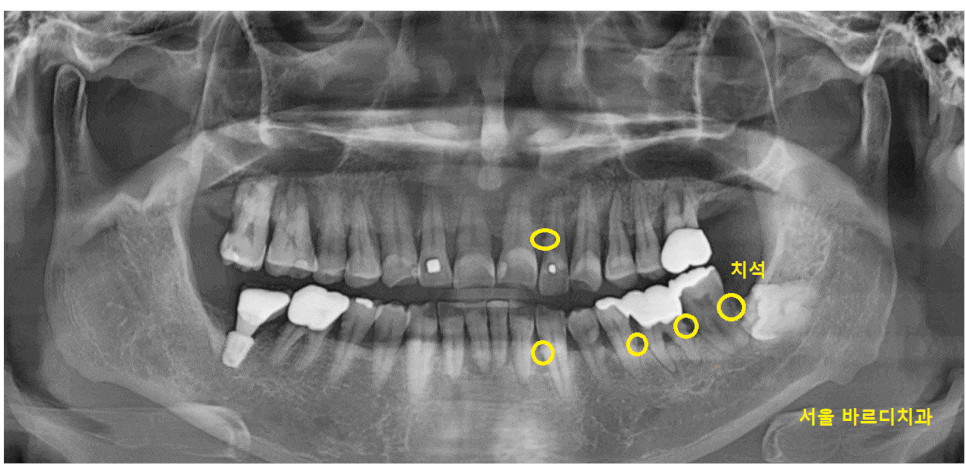

x-ray를 촬영해보니까

치석들이 x-ray 에 보일 정도로 많은 상황이었습니다.

22.12.16

잇몸 밖에 붙어있는 치석 외에도

뿌리쪽에도 있다는 얘기로

치석이 무지 많다는 말입니다ㅎㅎ